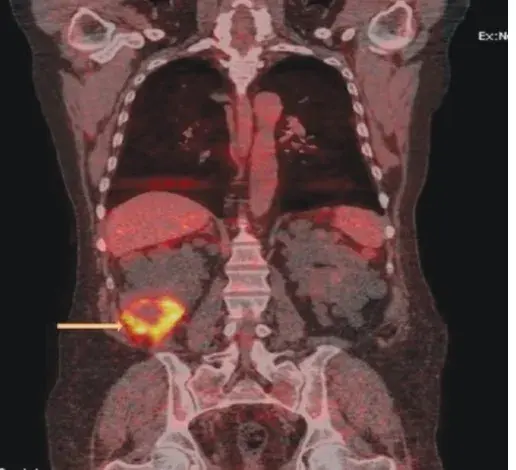

Após 04 após o último tratamento a paciente evoluiu com **novo** quadro de **edema nos membros inferiores**, **proteinúria** **de 8 g/dia** e **creatinina sérica de 1,27 mg/dl** (TFGe 37,5 ml/min/1,73m²), foi realizada uma nova biópsia renal (figura abaixo).